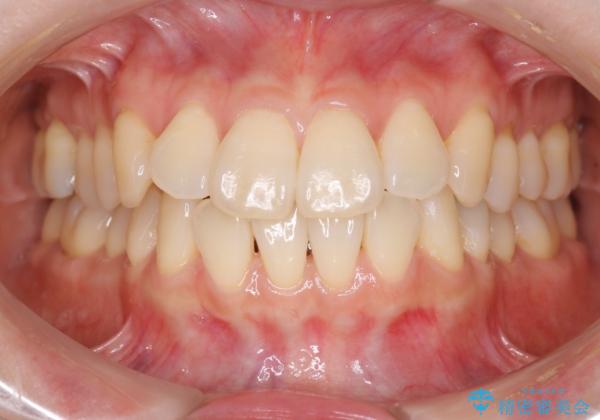

- インビザラインで非抜歯治療を行いました。IPRと拡大をし、叢生、咬合をきれいにしました。

主訴であったかみ合わせを正しい位置に動かし、バランスよくかめるようになりました。矯正治療終了後にメタルインレーをセラミックインレーに替えました。